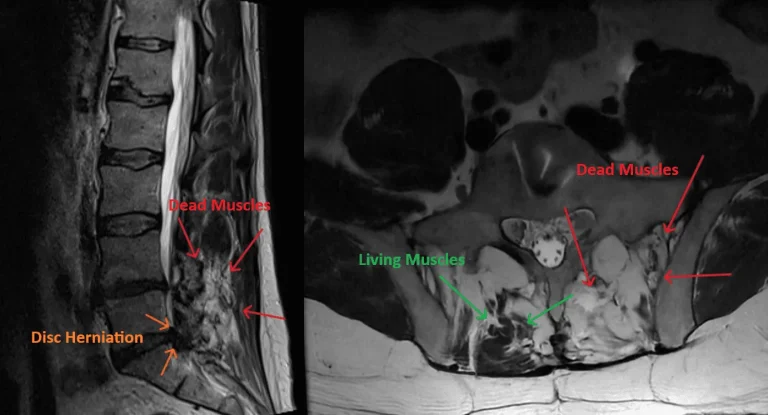

MRI scans show disc herniation and differences between dead and living muscles with labeled arrows.

Severe Post-Operative Pain